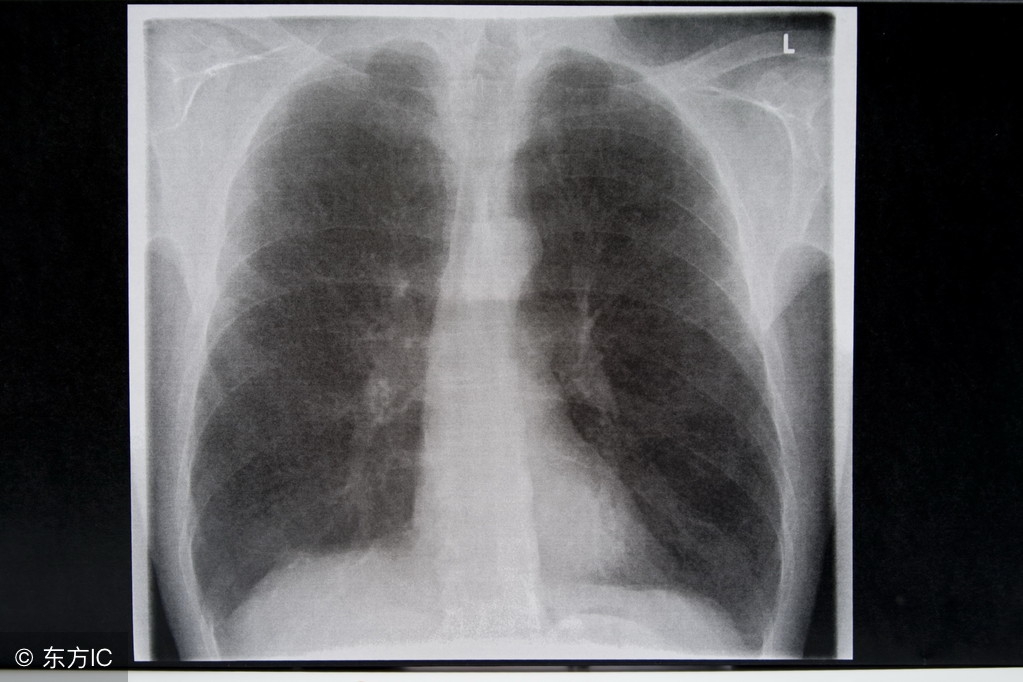

肺癌晚期可出现各个不同脏器的转移,可引起相应的症状,常常给病人带来极大的痛苦,甚至威胁到生命。肺癌的脑转移发生率较高可以达到35%~50%。